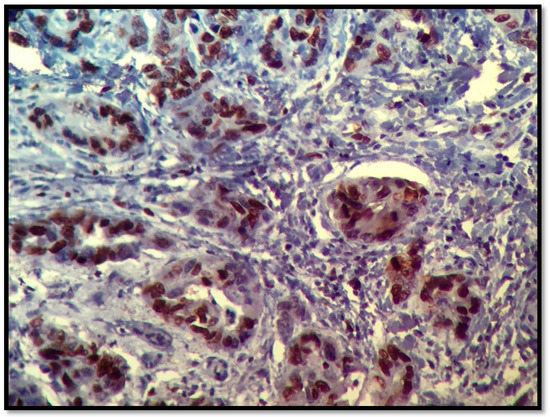

2.1. AR Assessment

3.1. Androgen Receptors

| IHC | AR ≥ 1% | Range |

|---|---|---|

| TNBC (n = 39) | 31 (80%) | 15–90 |

| R (−), Her 2/ neu (+), n = 22 | 14 (63% | 10–100 |

| R (+), Her 2/neu (−), n = 68 | 34 (50%) | 10–30 |

| R (+), Her 2/neu (+), n = 14 | 10 (71%) | 15–90 |